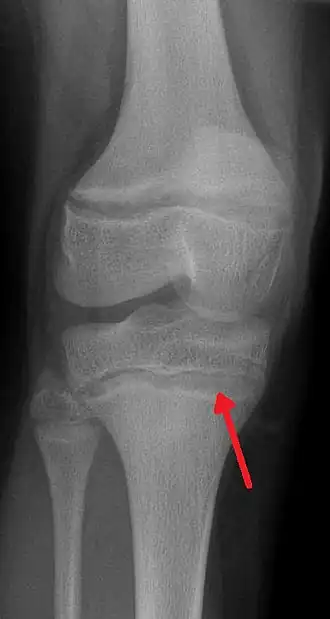

- dans les cas d'intoxication forte et/ou chronique, apparition d'un liseré grisâtre ou bleuâtre sur les gencives au niveau du collet des incisives et/ou canines, dit « Liseré de Burton » (très rare chez le jeune enfant, plus fréquent chez l'adulte gravement intoxiqué), taches jugales de Gubler[180], et apparition sur les radiographies osseuses d'une ligne blanche parfois dite métaphyséale sur les os longs, à la limite de l'os creux (diaphyse) et la zone de production du cartilage (ex. : image en haut à droite)[181] ;